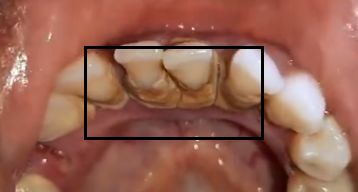

你的牙齿内侧还是像这样?

对不起,有点重口味了...

看看自己的牙齿有没有被牙结石包围...

而牙菌斑和牙结石日积月累后就会导致龋齿、牙龈萎缩、牙龈红肿、牙周病等一系列牙齿、口腔问题。

其实,这都是“假象”。牙结石是由牙菌斑堆积而成,其中的大量细菌会不断生长、繁殖,侵蚀牙龈,引发牙周炎等疾患。

如果长期不清理,牙龈会萎缩得越来越厉害,只会缩减牙齿的使用寿命。

简单总结:牙菌斑→牙结石→牙龈炎→牙周炎→牙齿松动。。。